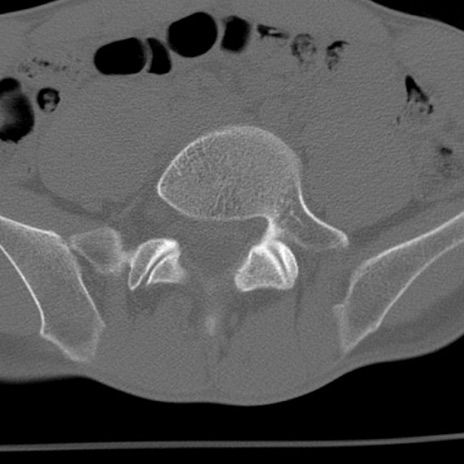

症例3 腰椎CT(横断像)

腰椎CT